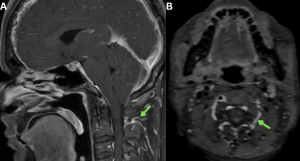

Fig 20: A 52-year-old man with a 6-month history of chronic orthostatic headache and progressive mid-thoracic discomfort, previously untreated for SIH.

Figure A: Axial T2-weighted image of the thoracic spine showing T2 hyperintensities in the region of anterior horn cells (red arrow) along with a T2 hyperintense anterior epidural fluid collection (green arrow).